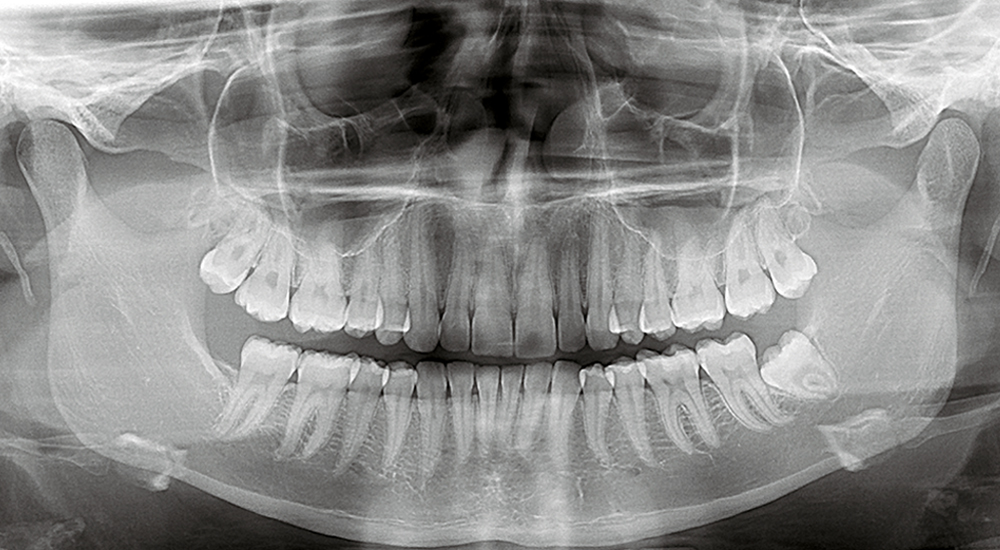

Digital Full Mouth Panoramic X-Ray

An Orthopantomogram (OPG), also known as an “orthopantogram” or “panorex”, is a panoramic scanning dental X-ray of the upper and lower jaw. It shows a two-dimensional view of a half-circle from ear to ear.